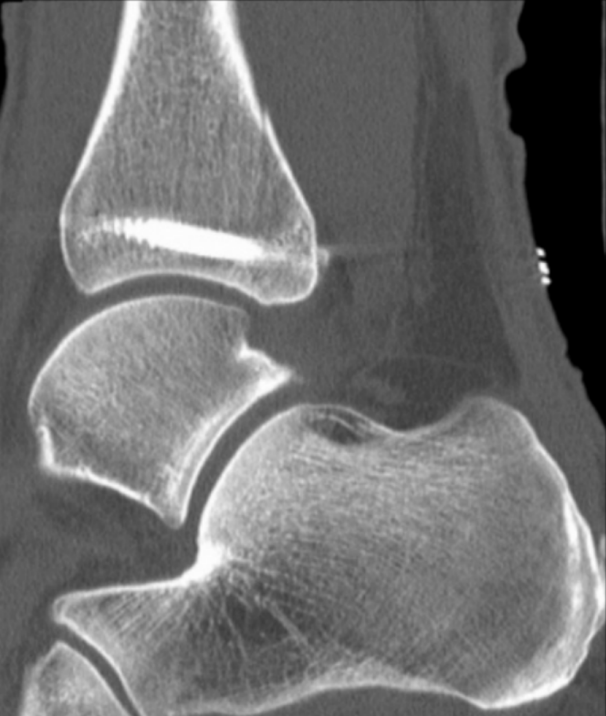

患者为83岁女性,于光滑平面滑倒后致三踝骨折,后踝为Bartonček 2型骨折,累及后外侧骨块及腓骨切迹(图2a–d)。相关合并症包括:骨量减少、软组织条件不良(皮肤呈羊皮纸样改变)、2型糖尿病(HbA1c 7.7%)。

图 2. (a–d):三踝骨折:(a) 前后位及 (b) 侧位X线片;(c) 轴位及 (d) 矢状位CT图像显示2型后踝骨折伴小中间骨块。

本例患者因高龄,无法安全使用助行器或遵守限制负重医嘱,故部分负重不可行。因此,早期活动是在无外部制动的情况下,根据耐受情况进行完全负重。出院前进行了术后CT扫描(图6)。

image.png

图 6. 术后CT扫描显示螺钉位置理想且解剖复位。